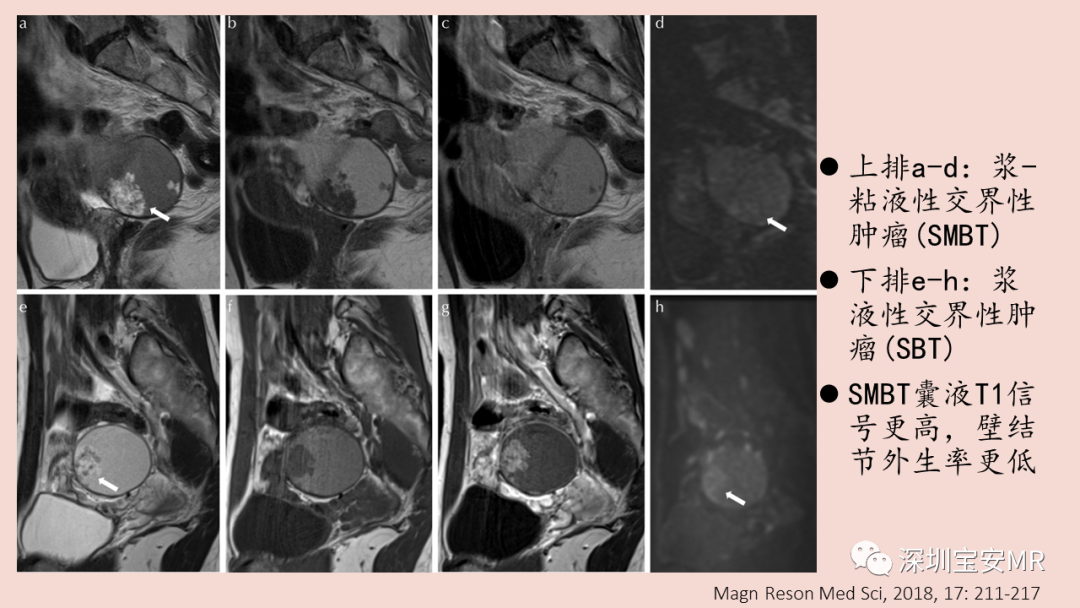

图片